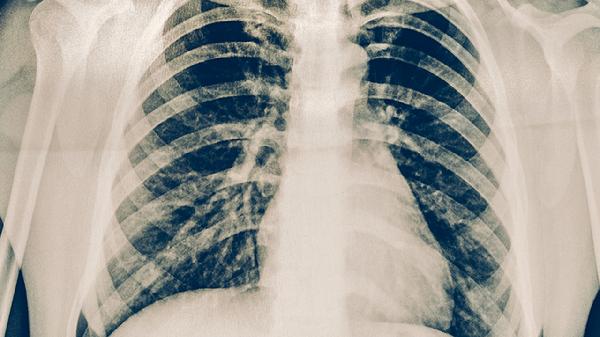

當(dāng)黃痰持續(xù)加重并出現(xiàn)高熱、胸痛或呼吸困難時,可能提示繼發(fā)細菌感染或病毒性肺炎。細菌性肺炎的痰液常呈深黃色或黃綠色,質(zhì)地黏稠且量多,肺炎鏈球菌等病原體在抵抗力下降時可能乘虛而入。這種情況需要及時進行血常規(guī)和胸部影像學(xué)檢查,若確診細菌性肺炎需使用抗生素治療,同時配合祛痰藥物幫助痰液排出。